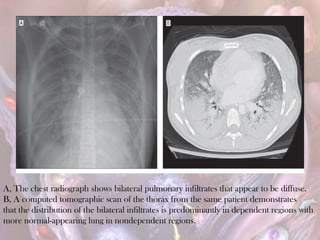

A, The chest radiograph shows bilateral pulmonary infiltrates that appear to be diffuse.

B, A computed tomographic scan of the thorax from the same patient demonstrates

that the distribution of the bilateral infiltrates is predominantly in dependent regions with

more normal-appearing lung in nondependent regions.